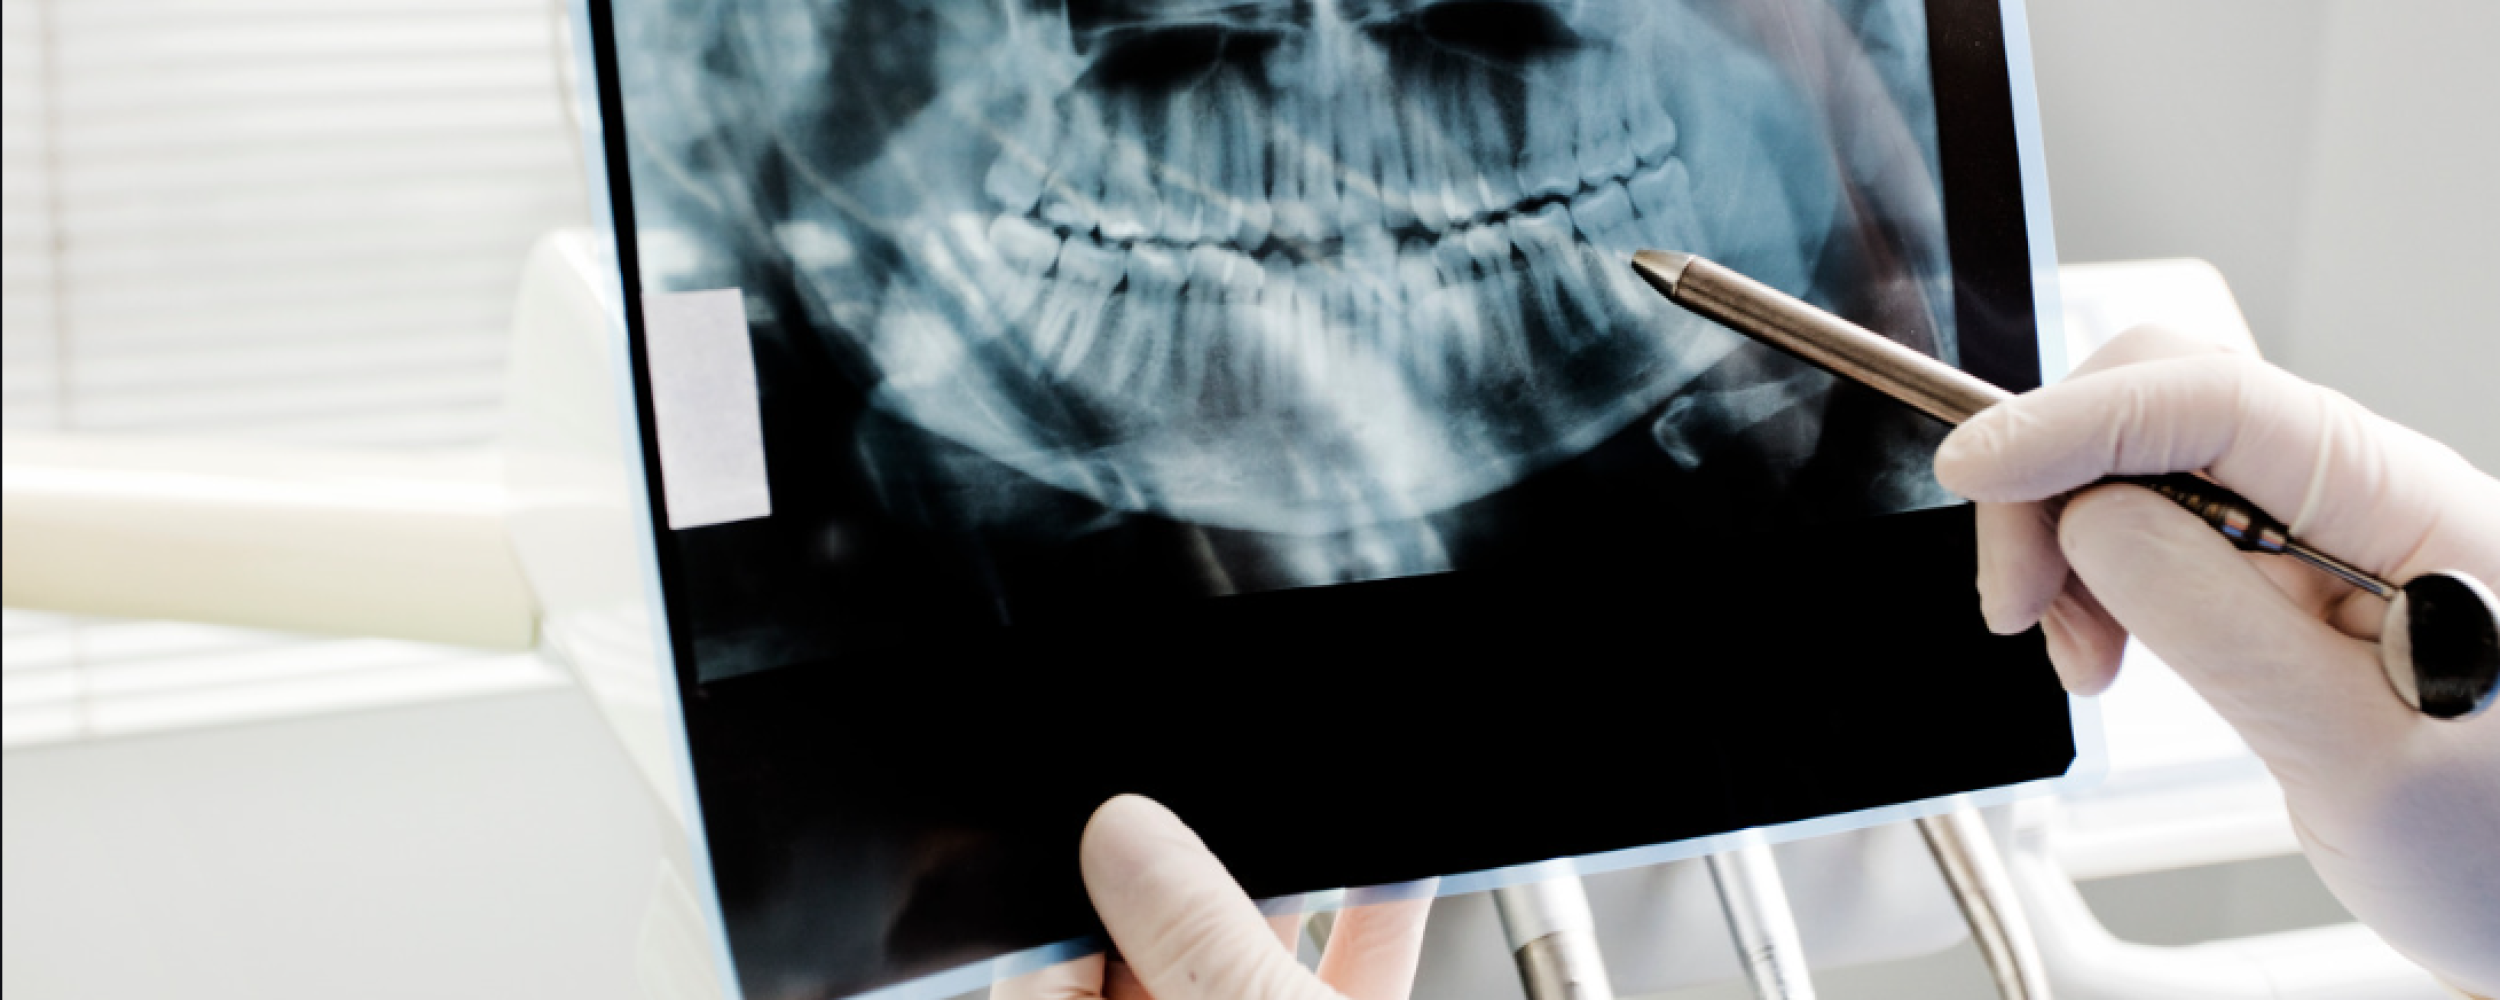

At Shenstone Dental Centre, we believe great dental care starts with using the right technology.

Investing in modern equipment allows us to make treatment more accurate, more comfortable, and often more efficient too. It helps us diagnose problems earlier, plan treatment more precisely, and give our patients a better overall experience from start to finish.

We use advanced dental technology across many areas of the practice, from digital imaging and scanning to treatments for dental implants, Invisalign, hygiene care and cosmetic dentistry. Every piece of equipment we introduce is chosen because it helps us deliver a higher standard of care.

Just as importantly, technology allows us to make dentistry feel more reassuring and less invasive. Whether that means avoiding messy impressions, improving comfort during treatment, or helping you understand your oral health more clearly, our aim is always to make your visit as smooth and stress-free as possible.